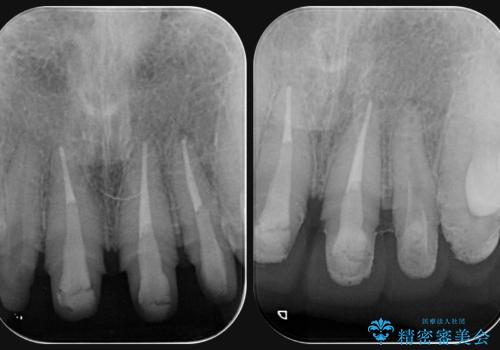

前歯には接着性の維持装置や、中途半端な形の連結クラウンが装着され、清掃性が悪く歯ぐきの腫れや、歯ぐきの形態の不揃いが認められました。

ただ、白いオールセラミッククラウンを製作・装着するのではなく、将来にわたり安定した状況を獲得するため、歯周外科を行い歯ぐきと周囲の歯槽骨の形態を整えていきます。